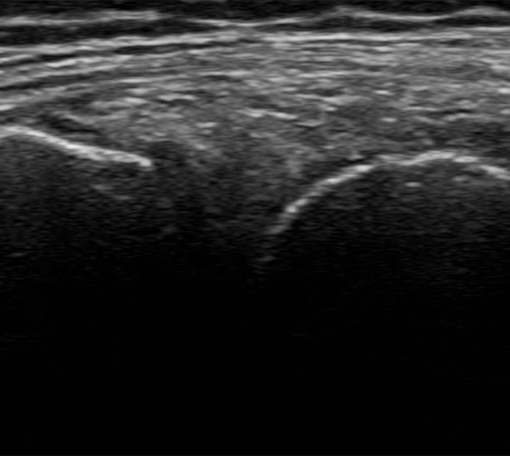

前腕~手関節部痛への超音波エコーガイド下鍼

前腕や手関節の筋・腱・神経を可視化し、細かな痛みの原因を特定。腱鞘炎や使い過ぎによる痛みに対応します。